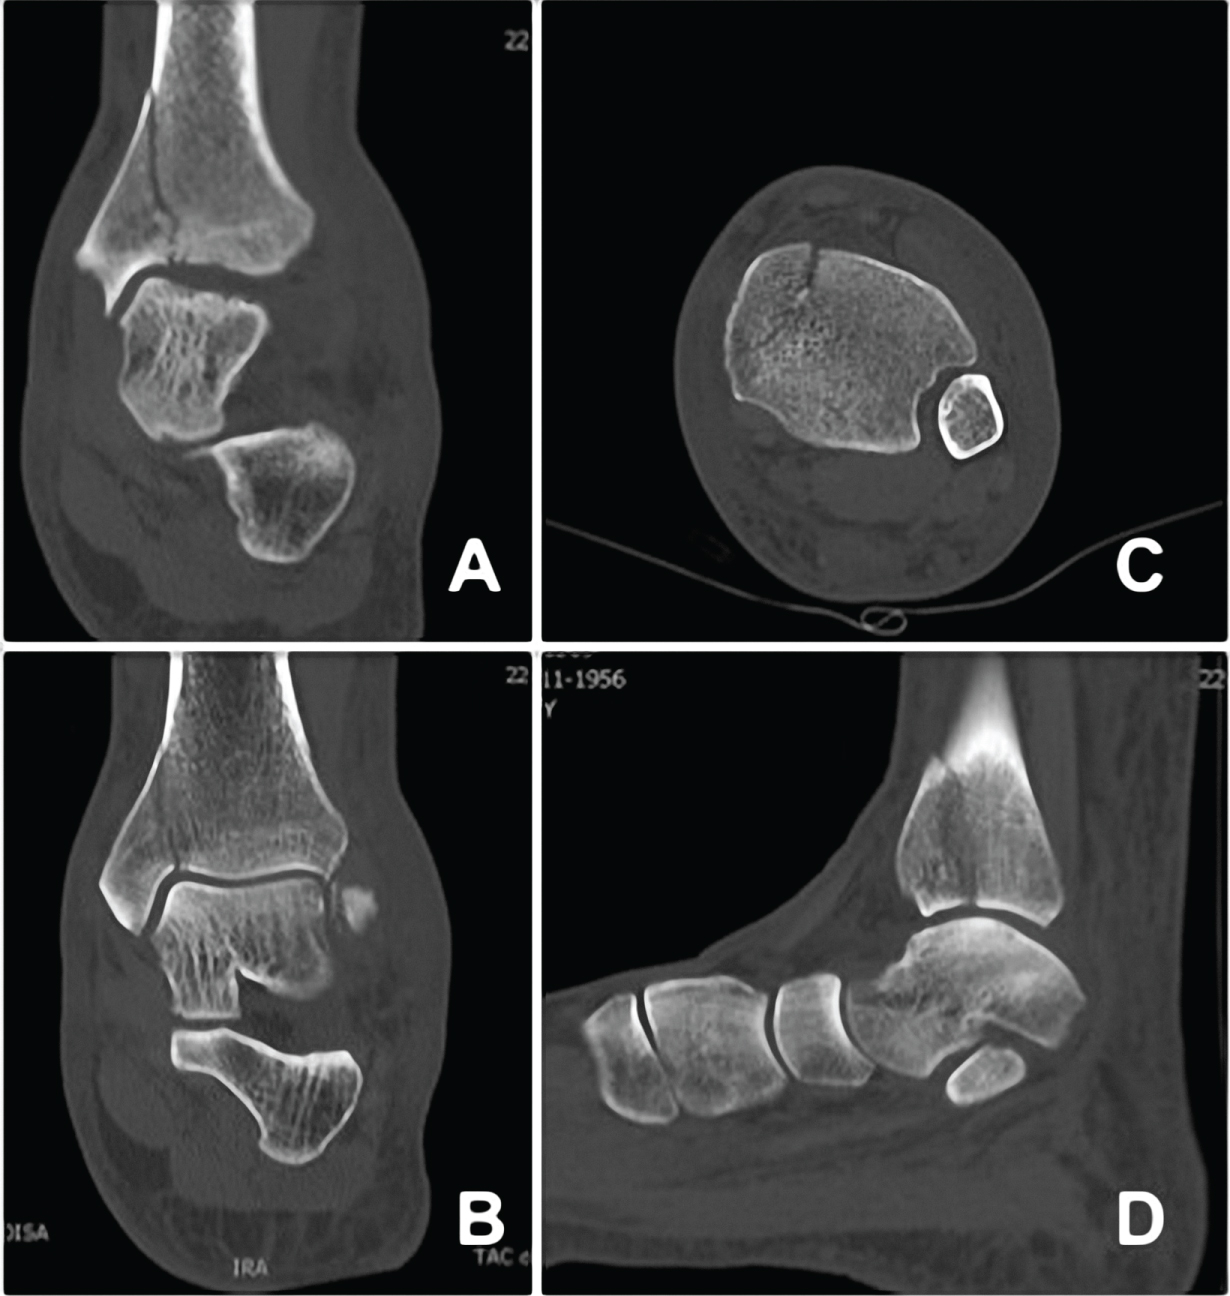

The patient's x-rays were reviewed, and a questionable radiolucent line was seen in the medial malleolus consistent with a fracture that had not been initially diagnosed (Figure 1). Ankle Computed tomography (CT) was performed, confirming the diagnosis (Figure 2).

Figure 2: Ankle CT-scan at presentation (A-D), Confirming the diagnosis. View Figure 2